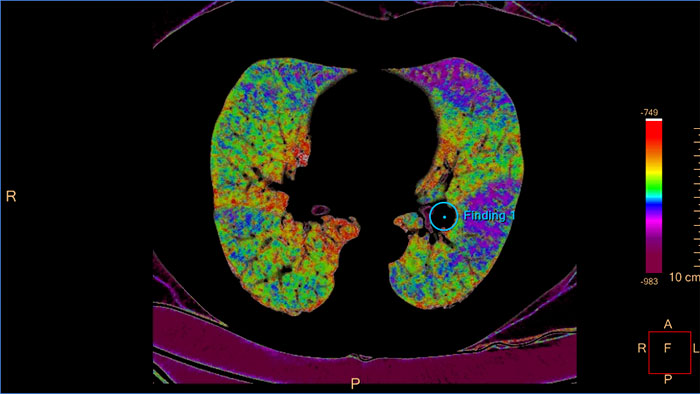

Quantify diffuse lung disease

CT COPD helps visualize and quantify the destructive process of diffuse lung disease (e.g. emphysema). The application provides a guided workflow for airway analysis, reviewing and measuring airway lumen, and assessing air trapped.